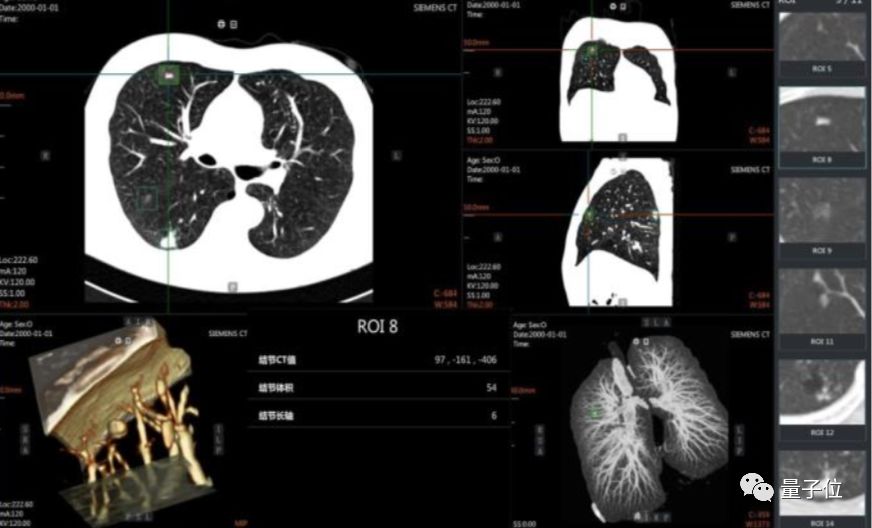

怎么进一步落地?英特尔提供了工具,比如OpenVINOTM工具套件以及至强处理器系列产品等等, 能够在在保证 U-net 模型高准确率的同时,推理时间大幅降低85%。

在报告中不仅给出了具体的使用方法,也放出了不少已经落地的案例,比如东软的eStroke溶栓取栓影像平台,西门子的心腔检测和量化模型等等。

与此同时,这也强化了影像数据的积累和分析,也让基于 AI 的医疗影像分析 应用日趋走向成熟,一个过去需要10分钟进行筛查的肺癌前期诊断,在AI的加持下能够达到秒级,而且准确率也在95%以上。

目前,在医疗影像 AI 分析应用中,目标侦测神经网络正被广泛地运用,其通过深度学习的方法,能够对 X 光片、CT 成像等医疗影像进行高效、准确的病灶检测。

实战手册中,在与西安盈谷 Cloud IDT 智能应用、医学影像处理及分析云计算@iMAGES 核心引擎等相结合后,在肺结节诊断等一大批关键场景中建立起“AI+Cloud”的智能辅助诊断系统能力。